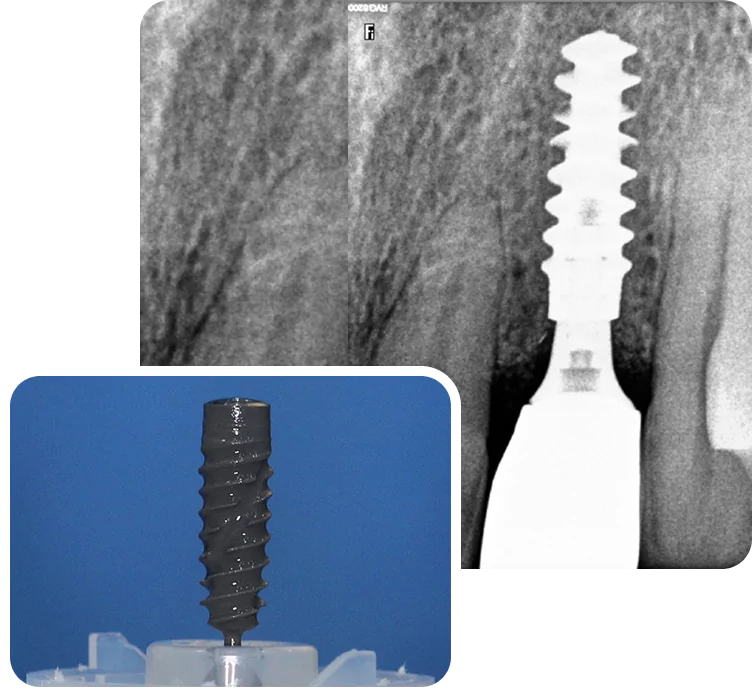

After a thorough clinical examination of your jaw bone, the Best dentist in Pune at Smilex confirms the available jaw bone by CBCT scan or X-rays. The doctors then administer a very small cut in the gums under local anesthesia. A painless drill sequence leads to the final drill position, after which the dental implants in Pune are placed in the bone. Gums are then placed back in their original position. A single implant procedure takes up to 45 mins to be done.

Single Tooth Implant

Single tooth implant are a simple and long-lasting way to replace one missing tooth. The implant is placed in the jawbone and acts like a root. A crown is attached on top to match the rest of your teeth. It looks real, feels strong, and helps you chew normally. Over time, it also helps prevent bone loss in that area. Unlike a dental bridge, it doesn’t rely on or damage the tooth next to it.

Standard Implant

Used when there’s enough bone in the area. A single titanium implant is placed in the jaw, followed by a custom crown once it heals. The tooth functions and looks natural.